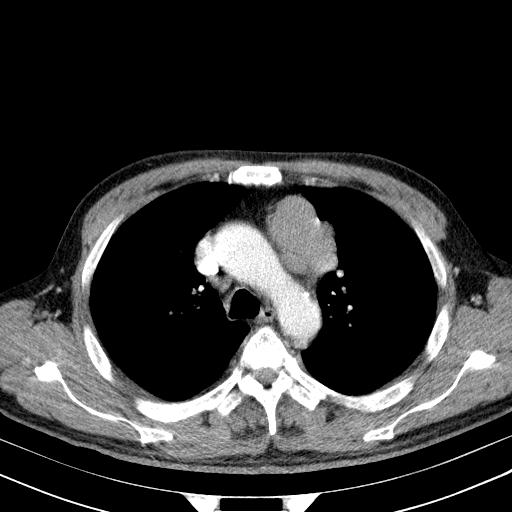

大家看看肝脏右叶片状低密度影是什么改变啊?

淋巴瘤?肝脏请增强后说啊

多发肿大淋巴结影,肝内改变需结合强化观察